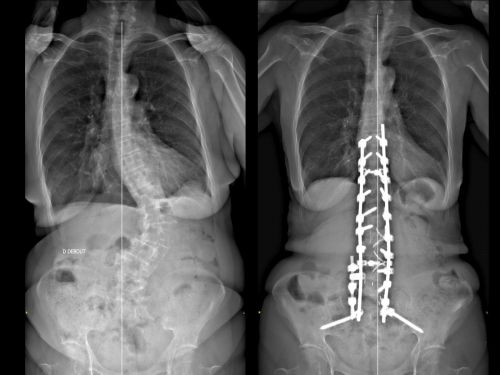

Une scoliose correspond à une déformation de la colonne vertébrale impliquant une déformation des vertèbres et des disques. Cette déformation est liée à la rotation de vertèbres. La rotation entraine une déformation dans les 3 plans de l’espace. La scoliose est une pathologie tridimensionnelle. Celle-ci s’apprécie d’abord cliniquement : se mesure par la gibbosité (en flexion du tronc, on mesure la différence entre les arcs costaux postérieurs). Cette gibbosité correspond à une déformation du dos en forme de « bosse ».

La radiographie de la colonne vertébrale nous apporte des informations complémentaires sur la scoliose, notamment avec l’angle de Cobb. Par définition, une courbure coronale de 10° ou plus (angle de Cobb) doit être présente pour diagnostiquer une scoliose. Lorsqu’une scoliose est diagnostiquée, un suivi régulier clinique et radiologique est primordial.

Pour ce type d’analyse, l’examen type EOS est une référence. Il correspond à une radiographie du rachis, de face et de profil, corps entier et permet de préciser l’équilibre global des patients dans le plan sagittal et le plan frontal. Un des paramètres importants pour l’évaluation d’une scoliose est l’angle de Cobb. Cet angle joue un rôle central. Ce paramètre permet de déterminer la gravité de la scoliose et permet également d’assurer son suivi. Ces données permettent d’avoir un suivi précis des patients afin d’ajuster la prise en charge en fonction de l’évolution. Associées aux paramètres fonctionnels, elles donnent des informations sur l’état structurel du patient, permettant une évaluation plus globale de la maladie vertébrale.